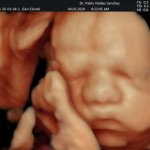

Los objetivos más importantes de esta ecografía son la evaluación de:

- La vitalidad y el bienestar fetal (Doppler).

- Crecimiento fetal.

- Las estructuras anatómicas fetales: diagnóstico de Malformaciones Estructurales de aparición tardía (displasias esqueléticas, alteraciones cardiacas pequeñas, alteraciones la vía urinaria y obstrucciones intestinales.